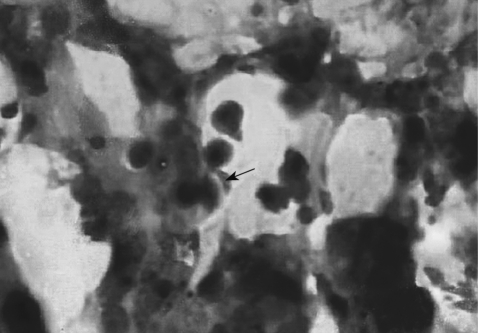

The presence of KI-1 tachyzoites in organs and tissues of infected mice was determined by light microscopy of histopathological slides (Table 1; Fig. 2) and by PCR using the B1 gene primer (Fig. 3). At the inoculum dose of 105 tachyzoites, tissue samples stained with Giemsa revealed T. gondii tachyzoites in the lungs and spleen at day 6 PI (Table 1; Fig. 2). In mice inoculated with 106 tachyzoites, tachyzoites were seen in sections of the liver and spleen at day 8 PI (Table 1). However, PCR appeared to be more sensitive than histopathology in detecting tachyzoites. In mice inoculated with 105 tachyzoites, the B1 gene was detected in the liver, lungs, stomach, kidney, MLN, and spleen on day 6 or 8 PI (Table 1). In mice inoculated with 106 tachyzoites, the B1 gene was detected in the duodenum and ileum as early as day 2 PI, and they continued to be detected in the duodenum on days 4, 6, and 8 PI (Table 1). The B1 gene was also expressed in the liver, jejunum, kidney, MLN, and spleen at day 8 PI. In both inoculum doses, there was no evidence of tachyzoite invasion into the brain in this experimental setting.

Section of the mouse lung showing a T. gondii KI-1 tachyzoite (arrow) at day 6 PI with 105 tachyzoites. Giemsa stain. ×1,000.

Fig. 2 Section of the mouse lung showing a T. gondii KI-1 tachyzoite (arrow) at day 6 PI with 105 tachyzoites. Giemsa stain. ×1,000.